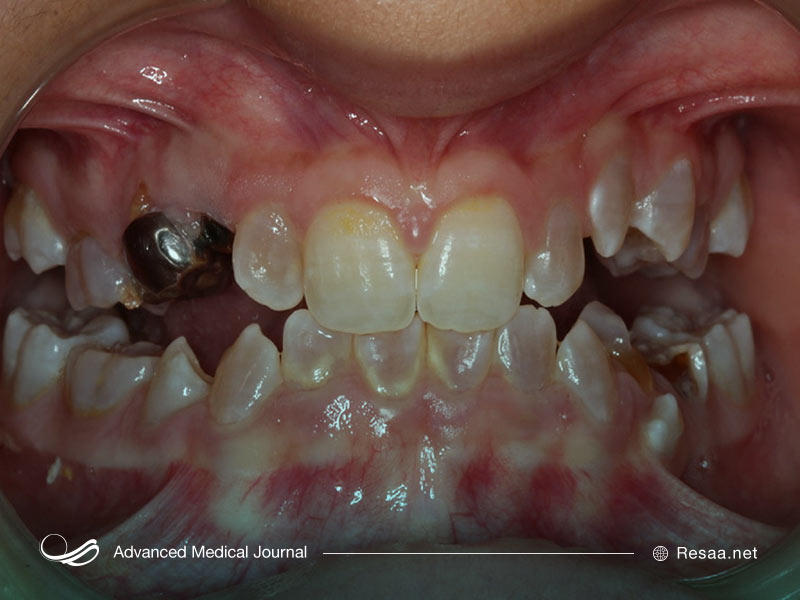

بیماری شکنندگی استخوان دارای یک یا چند مورد از علائم زیر است:

- دندانهای ضعیف

- مشکلات مربوط به تشکیل دندان (دندانپزشکی یا DI)

نوع 1 OI خفیفترین و رایجترین نوع بیماری شکنندگی استخوان است. در این نوع بیماری شکنندگی استخوان، بدن شما کلاژن با کیفیت خوب تولید میکند اما مقدار کافی از آن را تولید نمیکند. این وضعیت منجر به بروز استخوانهای شکننده با درجه خفیف میگردد. به طور معمول کودکان مبتلا به OI نوع 1 به دلیل ضربههای خفیف دچار شکستگی استخوان میشوند. چنین شکستگیهای استخوانی در بزرگسالان بسیار کمتر مشاهده میشود. این احتمال وجود دارد که دندانها نیز تحت تأثیر قرار بگیرند، در نتیجه ترک و حفره دندان ایجاد میشود.

معرفی نوع 4 OI